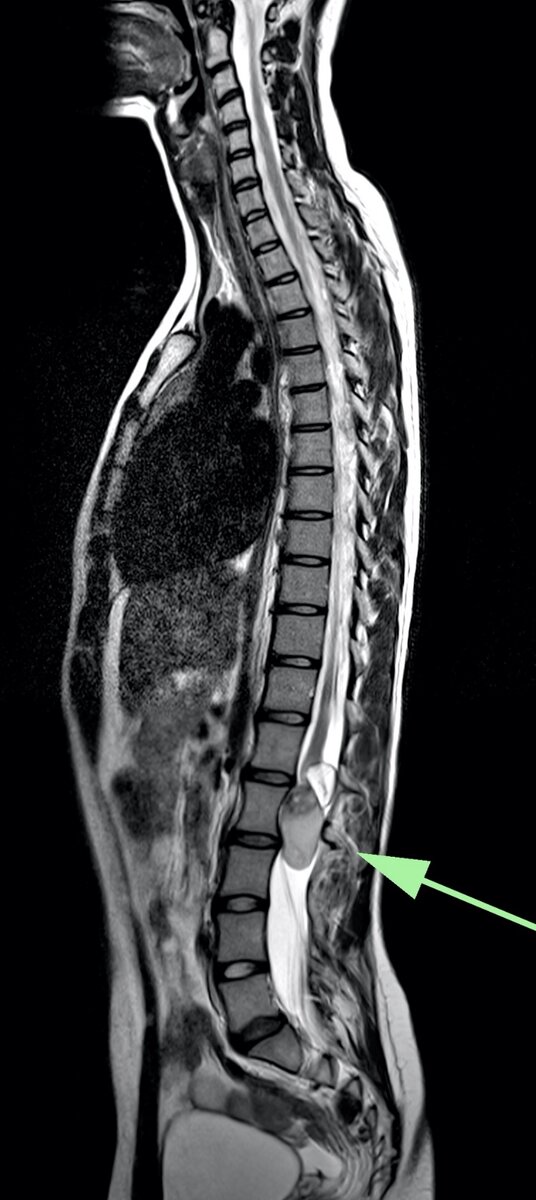

На МРТ обнаружена крупная опухоль конуса спинного мозга на уровне L1-L2 поясничных позвонков, тотально стенозирующая позвоночный канал. Структура опухоли неоднородная, с жировым компонентом. Спинной мозг и нервные корешки, идущие к ногам сдавлены. Это объясняет все её неврологические проблемы. Размер опухоли ≈ 6*3*3 см. Тем не менее, опухоль на МРТ выглядела доброкачественной, предположил дермоидную кисту.

Чтобы не терять время, сразу же дообследовали в в/в контрастным усилением.

Кракая справка: дермоидная киста (Dermoid cyst) - доброкачественная опухоль, в 20% процентов случаев возникает в нижних отделах спинного мозга. Пациенты обычно моложе 20 лет. Клинические проявления различные, в зависимости от размера опухоли; если её размер маленький то проявлений может не быть.

Золотой стандарт диагностики у таких пациентов - МРТ.

Опухоль, как правило, имеет характерную структуру с включениями жира, что отлично видно на МРТ.